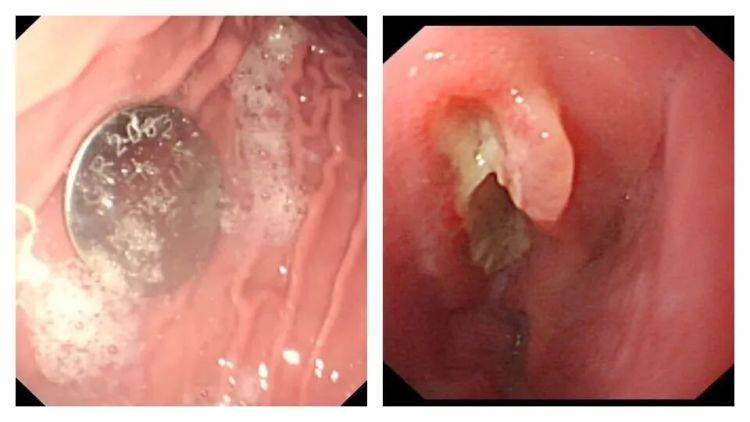

医生利用胃镜取出了卡在食道的电池,但距离孩子吞下电池已经过去10个小时,孩子的食道被电池释放的化学物质腐蚀并穿孔。

△图源:南京市儿童医院

南京市儿童医院消化科副主任医师练敏介绍,电池取出两周后,造影发现宁宁被灼伤的食道因瘢痕形成狭窄,导致吞咽困难,落下终身残疾。后续医院又多次对宁宁进行食道扩张治疗,尽可能恢复食道功能。